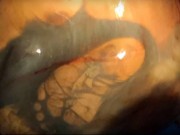

Video thai nhi 26 tuần nhảy múa trong bụng mẹ

Chia sẻ trên facebook cá nhân cách đây không lâu, bác sĩ phụ sản từ lâu đã được nhiều người ví đẹp như tài tử Hàn Quốc Trần Vũ Quang (Bệnh viện Phụ sản Trung ương) đã đăng tải clip ngắn về hình ảnh thai nhi 26 tuần đang nhảy múa trong bụng mẹ.

"Những cái đạp, những cú máy nhè nhẹ của con trong bụng mẹ là sự "giao tiếp" đầu đời mà mẹ vô cùng trân trọng. Động tác thai máy giúp mẹ yên tâm rằng em bé khỏe và con vẫn đang phát triển từng ngày.", bác sĩ Quang viết.